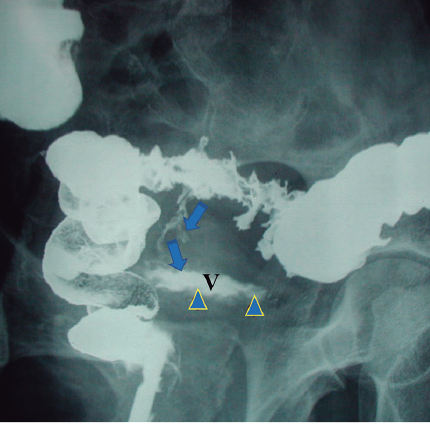

José Ángel Zamora-Soler, Vanesa Maturana-Ibáñez